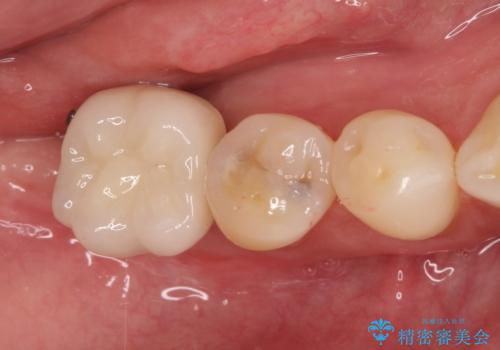

- 奥歯が破折していたため、抜歯を行ったあとインプラントを埋入して咬合回復を行っております。

- 1年

- 5-10回